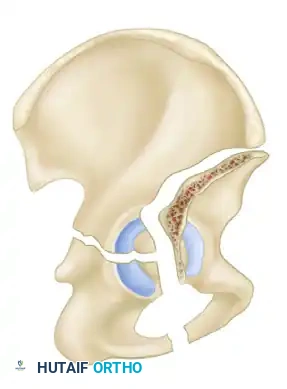

- T-Shaped Fractures: A transverse fracture with an additional vertical fracture line that splits the inferior ischiopubic segment, exiting through the obturator ring.

Incarcerated Intra-Articular Fragments

Following the closed reduction of a hip dislocation, a post-reduction CT scan is mandatory. While small avulsions of the ligamentum teres sequestered deep in the cotyloid fossa may be observed, any osteochondral fragment lodged between the articulating surfaces of the femoral head and the acetabular dome necessitates urgent surgical excision and joint irrigation.